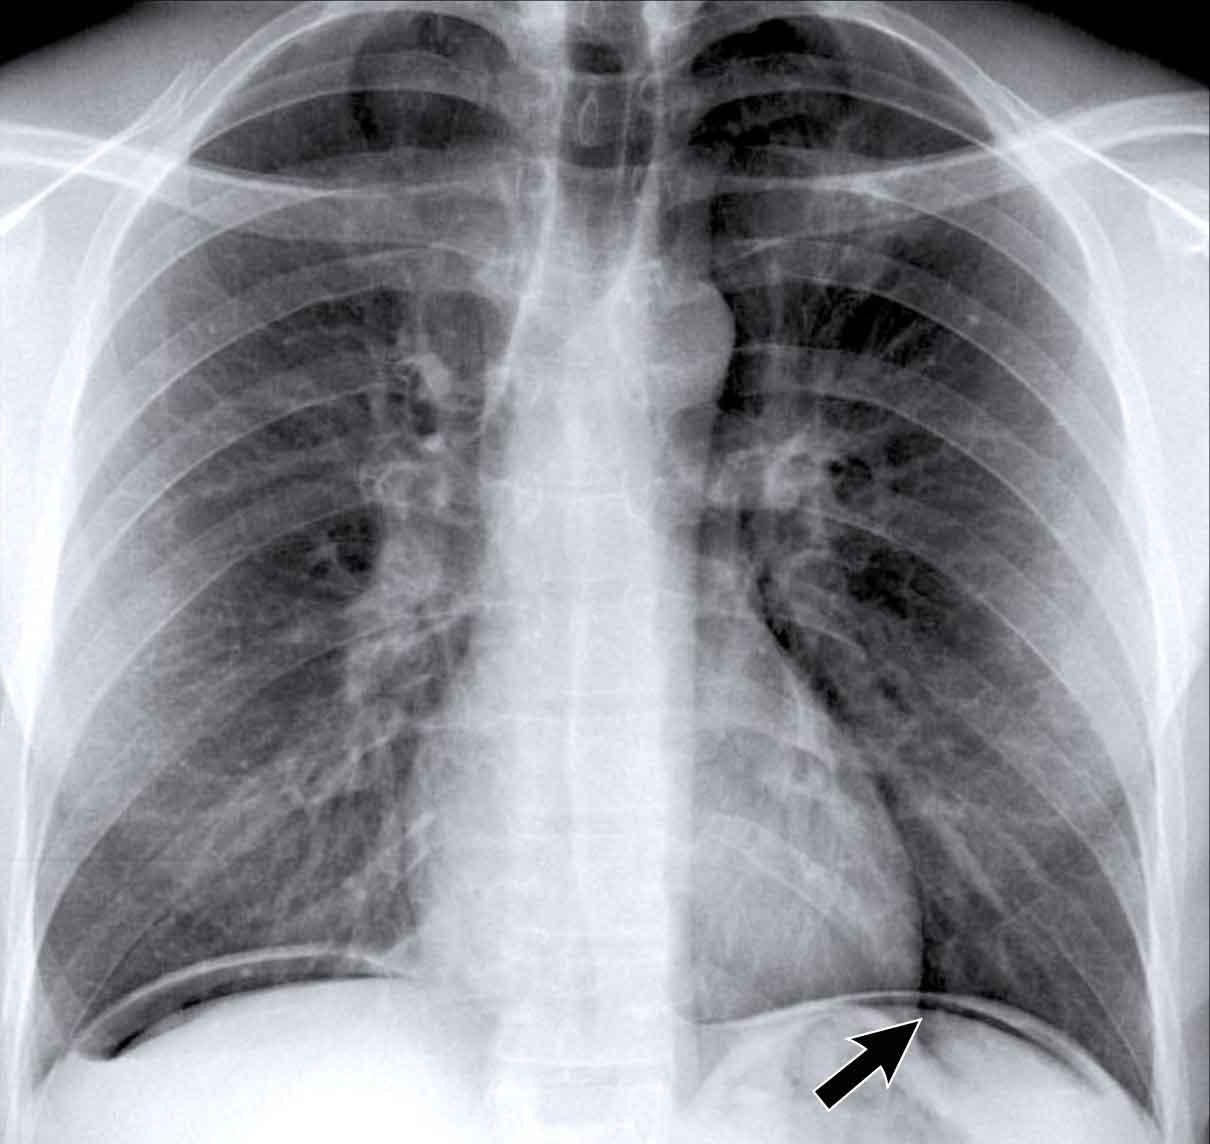

Another Example of Free Air

• A second patient presents with free subdiaphragmatic air.

• A thin, well-defined diaphragmatic contour is visible (arrow), differentiating it from plate-like atelectasis, which may mimic this appearance in cases of suboptimal inspiration.